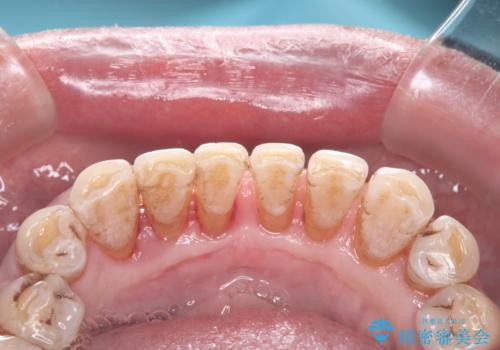

- 歯周病が進行されていているため歯肉が下がり歯根も露出してるためブラッシングが大変とのこと。

プラークや歯石が付着しやすい。

歯茎の中にもある歯石を何回かに分けて除去。

磨いているが磨けていない状況が分かりブラッシング指導や定期的なメンテナンスの重要性を理解されていました。

中程度から重度の歯周病で初期治療が終わりこれから定期的なメンテナンスをしていく予定です。